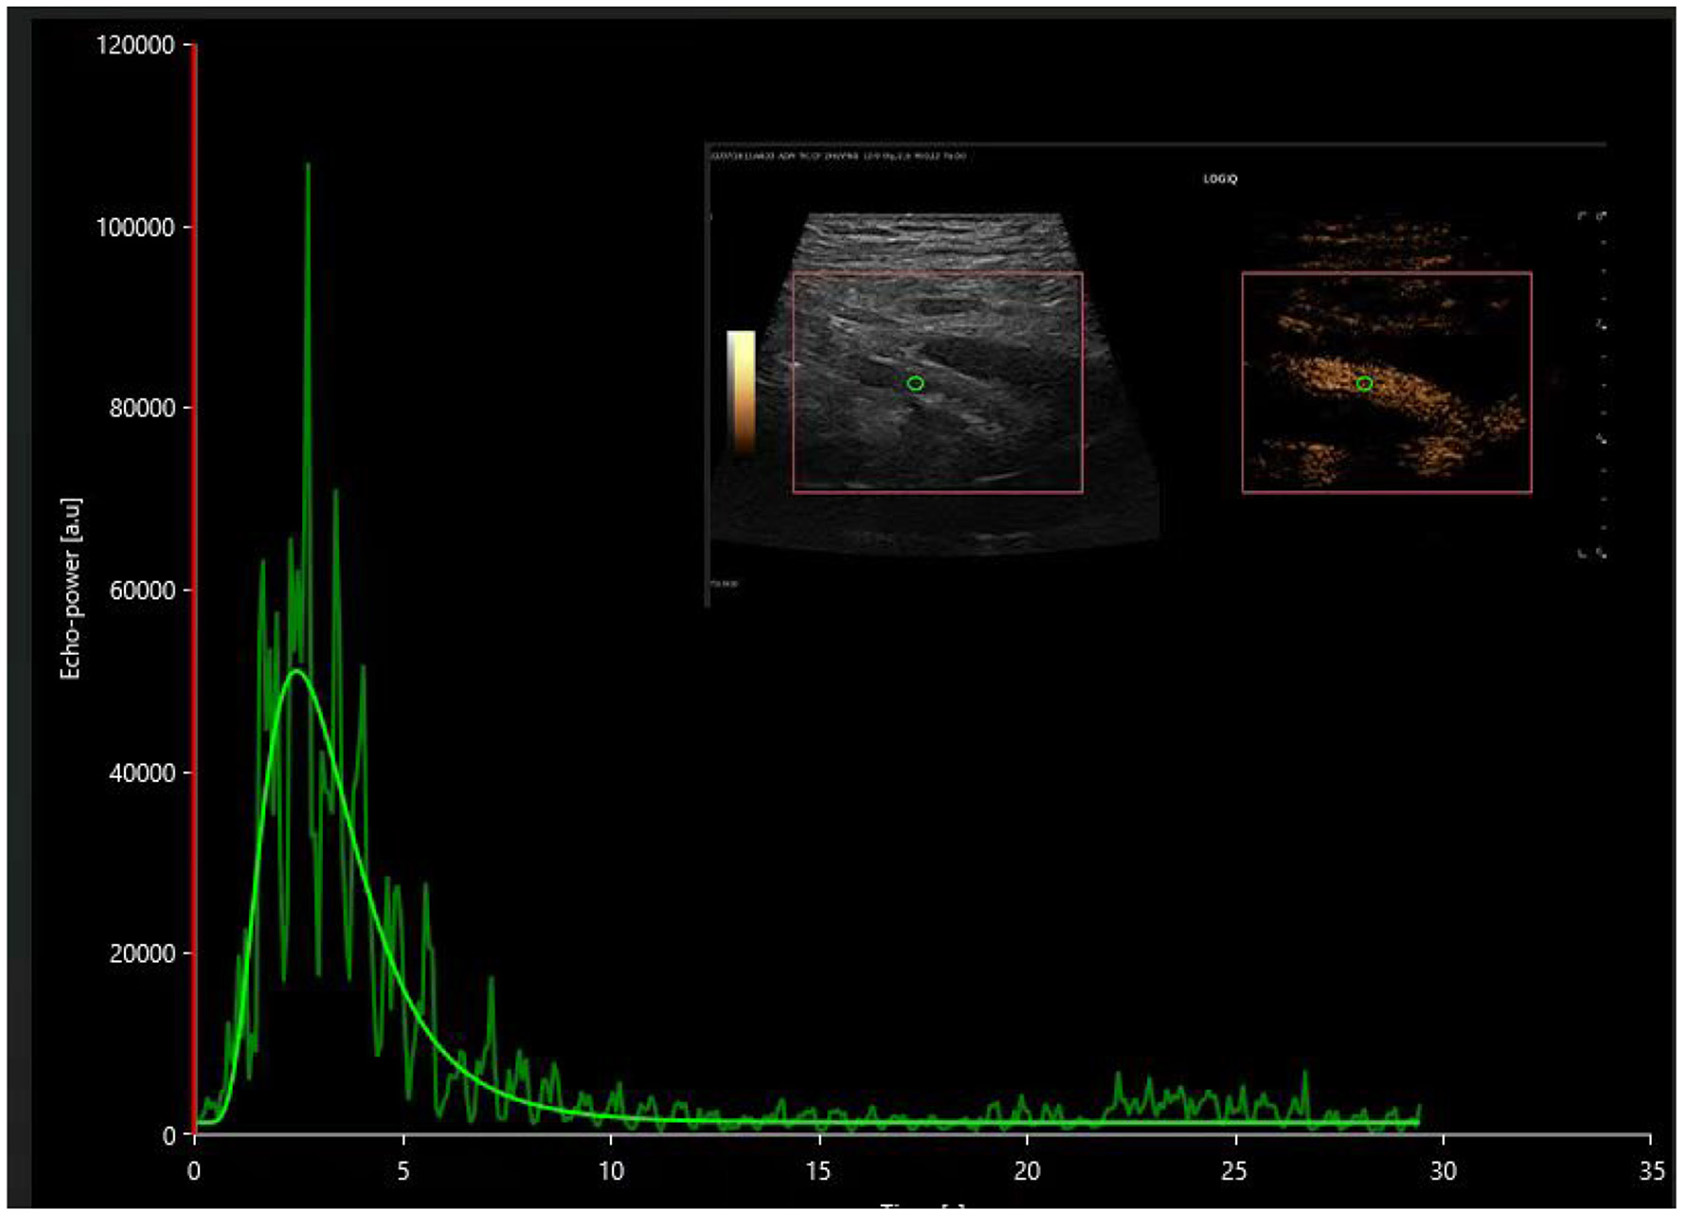

The investigation utilized contrast-enhanced ultrasound along with VUEBOX quantitative analysis software to determine that the time to peak (TTP) in both the cortical and medullary regions of interest showed prolonged durations in the DGF cohort compared to both the stable renal function cohort and the AR cohort, indicating statistically significant differences (P < 0.05). These findings can be employed to distinguish between DGF and AR, as the TTP in the cortical and medullary regions in the DGF group was significantly extended compared to the AR group, as illustrated in Figures 2, 3. The reduced rate of enhancement of the contrast agent within the transplanted kidney suggests that delayed recovery of renal function may be due to increased microcirculatory resistance and uneven distribution of resistance, leading to significant delays in the inflow of the contrast agent (18). This finding aligns with previous studies. Moreover, this study identified four distinct regions of interest and found that different regions reflected varying perfusion conditions within the transplanted kidney. Nonetheless, parameters within the cortical and medullary regions seem to better capture differences in microcirculatory blood flow perfusion within the transplanted kidney. This suggests that during contrast-enhanced ultrasound examination, increased resistance hinders the entry of the contrast agent from the cortex into the medulla in the transplanted kidneys of the DGF cohort, consistent with its pathological changes (19, 20).

Figure 2

Postoperative time-intensity curves of contrast-enhanced ultrasound in the DGF group, with regions of interest (ROIs) highlighted for the cortex (yellow), medulla (pink), and a combination of partial cortex and medulla under the large capsule (green).

In this investigation, all renal transplant procedures were executed utilizing an end-to-side anastomosis technique, with complications pertinent to renal vasculature arising from transplantation surgery being systematically excluded. In patients exhibiting stable recovery of renal function, contrast-enhanced ultrasound unveiled a sequential enhancement pattern, progressing from the iliac artery to the main renal artery, interlobar artery, interlobular artery, and arcuate artery. Employing the perfusion pattern of the main renal artery in the AR group, as illustrated in Figure 4, as a reference, we analyzed the perfusion pattern of the main renal artery in the DGF group, as depicted in Figure 5.

The time-intensity curve of the main renal artery on contrast-enhanced ultrasound in the postoperative DGF group.

This study first discovered significant differences in CUES parameters in the region of interest of the main renal artery in transplant kidneys. All renal transplant procedures were performed using an end-to-side anastomosis technique, and complications related to renal vasculature caused by the transplantation surgery were excluded. In patients with stable recovery of renal function, contrast-enhanced ultrasound revealed sequential enhancement of the iliac artery, main renal artery, interlobar artery, interlobular artery, and arcuate artery. In the cohort experiencing delayed graft function (DGF), the sequence of contrast enhancement within the transplanted kidney mirrored that observed in the stable renal function cohort, albeit with a notably diminished rate of enhancement. The presence of renal vascular resistance during renal dysfunction may lead to the cessation or even reversal of blood flow within the renal artery and interlobar artery during diastole (21, 22).

This investigation observed a higher renal artery resistance index (RI) in the DGF group using two-dimensional ultrasound, even in the absence of diastolic reflux. Such observations could potentially be attributed to the limited sample size and possible errors introduced by variations in patient heart rate, blood pressure, and angles. Nonetheless, contrast-enhanced ultrasound imaging of the main renal artery and subsequent quantitative analysis using VUEBOX software revealed a statistically significant prolongation in time-to-peak (TTP), rise time (RT), and fall time (FT) within the main renal artery in the DGF group compared to both the stable renal function and acute rejection cohorts. This difference may be due to pathological changes in patients with delayed graft function (DGF), such as detachment of tubular epithelial cells, renal enlargement, and increased renal tension, leading to increased microvascular resistance.